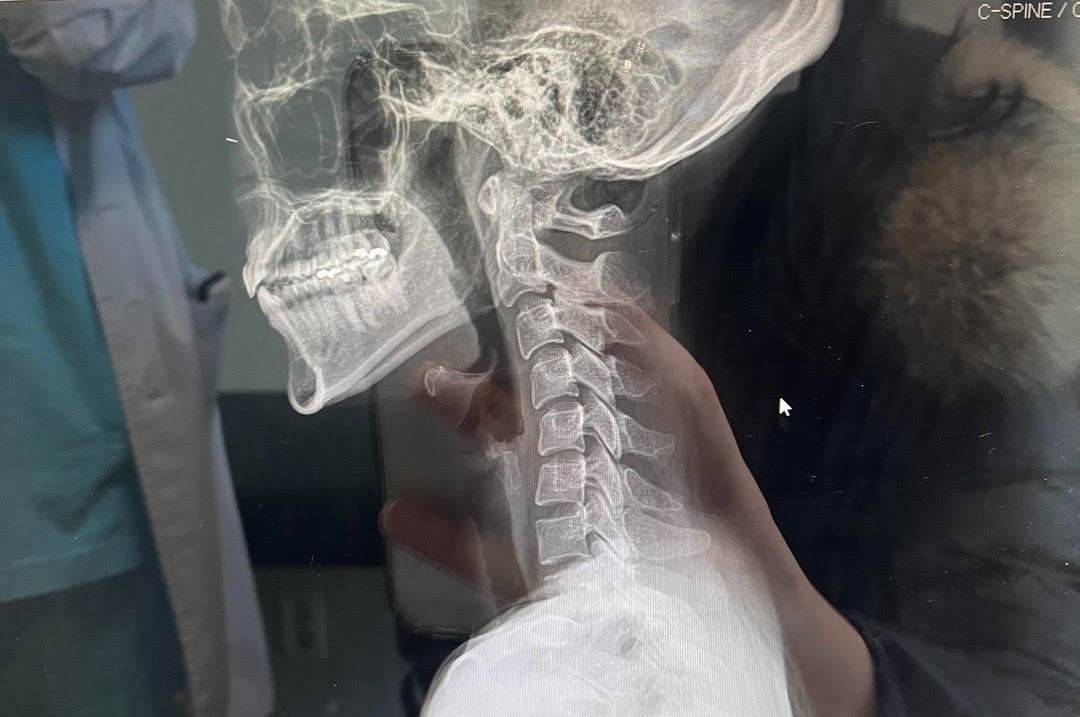

통증의학과 진료 시 찍었던 X선 촬영. 일자목을 넘어서 역C자목이란다. 모니터를 보여주며 사진을 찍어가라고 하셨다.

올 가을 건강검진에서 경추CT를 선택했고, 디스크 전단계라는 추간판 팽윤이라는 진단이 떴다.